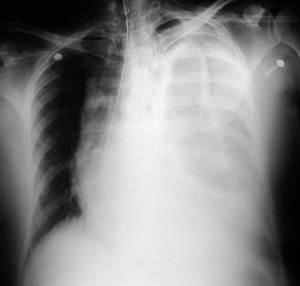

• Radiología del Tórax

Rx. tórax. PA y Lateral Izquierda

Rx. Tórax al momento de su Ingreso. radiopacidad difusa del hemitorax izquierdo conteniendo asas delgadas dilatadas con edema de la pared intestinal, desviación mediastinica contra lateral, disminuyendo por compresión del volumen torácico derecho, en la Rx lateral imágenes de niveles hidro-aereos múltiples , con discontinuidad diafragmática izquierda.